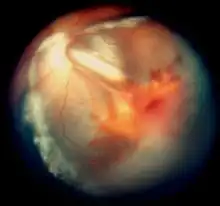

Exudative retinopathy and vitreous hemorrhage in cerebroretinal microangiopathy with calcifications and cysts

Vitreous hemorrhage and exudative retinal detachment resembling Coats' disease in a child with cerebroretinal microangiopathy with calcifications and cysts

Smaller blood vessels of the retina are abnormally developed and appear tortuous and dilated to a variable extent, typically in one sector and mainly in the peripheral and temporal portions of the retina.[1][2][3][9] This is known as telangiectasia. The vessel walls are weak and leak blood plasma and lipid within and underneath the retina. This leakage can lead to exudative retinal detachment, also known as exudative retinopathy in this context. The detachment typically has a yellowish tint because the fluid under the retina contains lipid. These findings mimic Coats disease.[9] Characteristically, the abnormal vessels are localized and the retinal blood vessels peripheral to the abnormal ones seemingly have failed to develop and are thus not seen.

In some eyes, retinal vessels form small nodules on the surface of the retina, known as angiomas.[1] These can bleed and be attached to the vitreous humour. The attachment can cause traction retinal detachment.